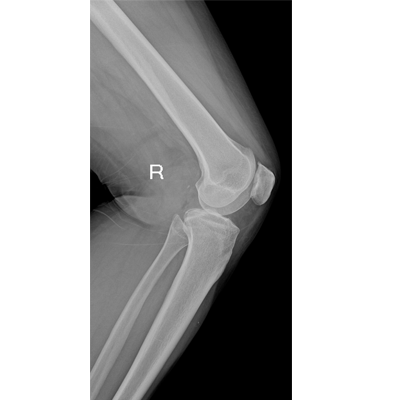

輕量化設(shè)計(jì) 小巧靈活 PLX5100

用于影像科、急診室、病房、ICU、手術(shù)室等多場(chǎng)景應(yīng)用。

● 數(shù)字化無(wú)線平板成像,操作簡(jiǎn)便,成像質(zhì)量高